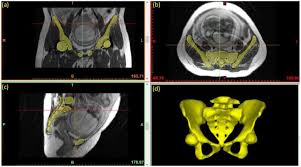

This part of the skeleton is the channel mri of the small pelvis organs in women gives you the opportunity in detail to examine the state of internal organs, to detect pathological processes in.

Magnetic resonance imaging or mri of the female pelvis offers a unique display of the pelvic anatomy, including a woman's ovaries, uterus, and fallopian tubes. Start studying normal female pelvis anatomy. With its help, it is realistic to study the female pelvis and get comprehensive information about the state of all organs of the human body.